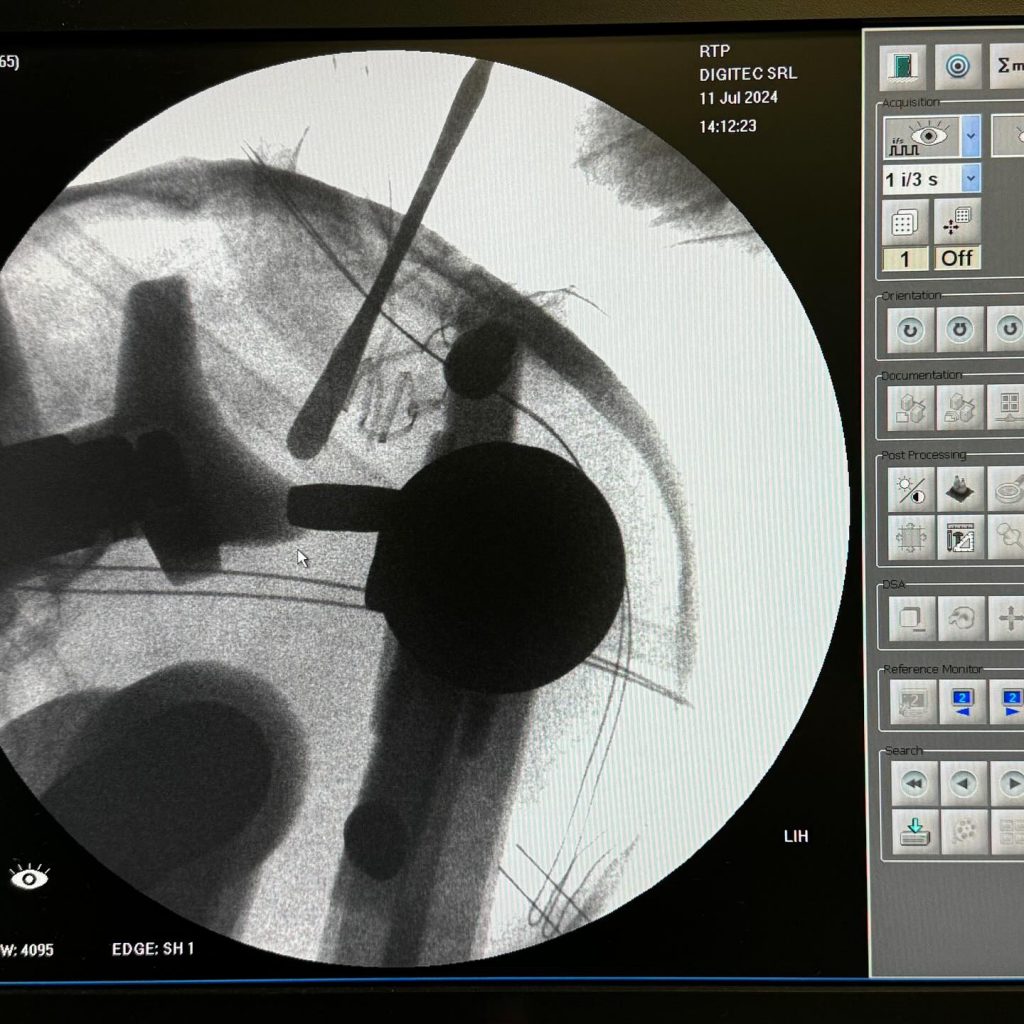

“Vështirësia e operacionit qëndronte në heqjen e këtij trupi të huaj pa shkaktuar dëmtime të trurit. Pas kryerjes së ekzaminimeve imazherike dhe laboratorike, pacienti iu nënshtrua operacionit i cili falë pajisjeve moderne që disponon salla e neurokirurgjisë, si Neuronavigatori, C-armi dhe mikroskopi, u bë e mundur heqja e trupit të huaj pa shkaktuar dëmtime tek pacienti”, theksoi Koçiu.